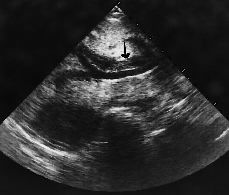

Abdomen La ecografía abdominal en los pacientes con sida

Abdomen Abdominal ultrasound in AIDS patients